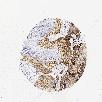

CANCER LUNG CANCER Show tissue menu

KRT18 is potential prognostic, high expression is unfavorable in Lung Adenocarcinoma (TCGA)